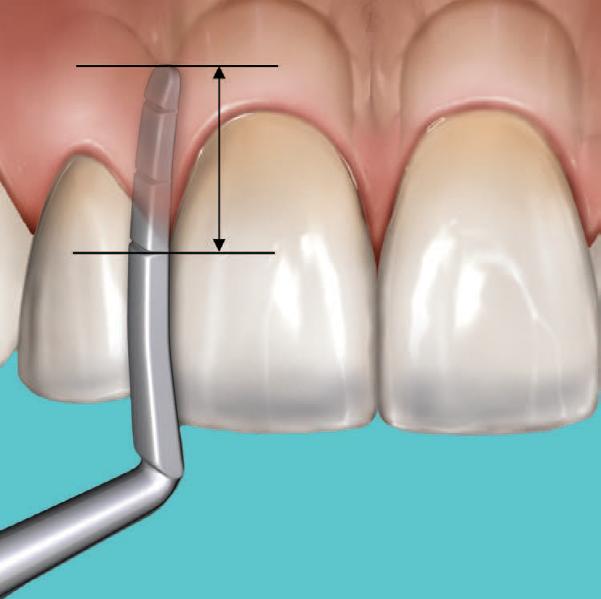

Why immediate dentine sealing?

Resin infiltration into the dentine surface is more effective on freshly cut dentine because it is uncontaminated and clean. Immedciate Dentine Sealing protects dentine against contamination with bacteria or remnants of temporary cements. It prevents post-operative sensitivity by sealing dentine tubules. It increases bond strength of the final indirect restoration to the tooth. It often eliminates the need for anaesthesia during the cementation procedure (when the restoration is delivered in the next appointment).

• When doing immediate dentine sealing with G-Premio BOND, it is recommended to add a thin layer of G-aenial® Universal Injectable or a flowable composite on top.